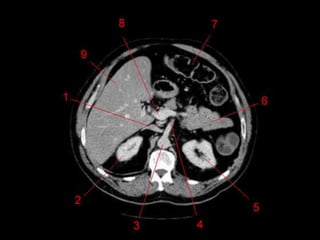

Lobos Anatômicos

• Lobo Direito e Esquerdo

– Dividido pelo ligamento falciforme.

• Lobo Quadrado e Lobo Caudado

– Fissuras sagitais esquerdas e direitas e divididos

pela porta hepática.

– Lobo Caudado é superior ao lobo quadrado.

Lobos Anatômicos • LoboDireito e Esquerdo – Dividido pelo ligamento falciforme. • Lobo Quadrado e Lobo Caudado – Fissuras sagitais esquerdas e direitas e divididos pela porta hepática. – Lobo Caudado é superior ao lobo quadrado.